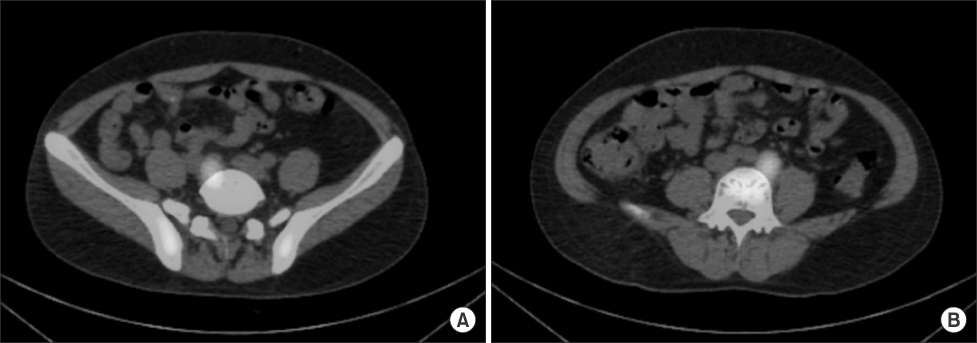

Fig. 1

Abdominal MRI shows two homogeneous enhancing masses in both common iliac area (arrows). (A) Right side. (B) Left side.

Fig. 1 Abdominal MRI shows two homogeneous enhancing masses in both common iliac area (arrows). (A) Right side. (B) Left side.